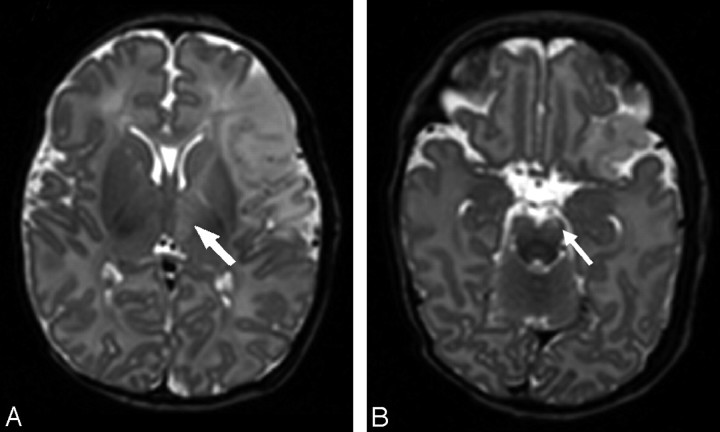

Fig 6.

T2-weighted images of a patient with an infarction within the anterior MCA branch territory on day 5 (patient 15) show high SI changes within the ipsilateral thalamus (arrow, A) and the ipsilateral brain stem (arrow, B).

On T2-weighted images, the cortex in the region of infarction was initially of high SI but became low SI after day 6. Loss of cortical tissue in the areas of infarction was seen from day 14 and was most marked after 1 month. During the period of 1–2 months of age, there was no difference in SI compared with the contralateral side in the remaining tissue (Fig 4). The white matter was of high SI on T2-weighted images until 2–3 weeks of age (Fig 5), when the SI of the remaining tissue became isointense with the contralesional side. Tissue atrophy often with cyst formation was evident after 1 month but started between 14 days and 1 month. The basal ganglia were of high SI in the first 4 days and became low SI from day 4 until day 7. From day 7 until day 14, we saw a checkerboard pattern, and after 1 month, atrophy or cysts were seen (Fig 3). During the study period, a higher SI was seen in the ipsilateral PLIC in 9 patients compared with the contralesional PLIC, suggesting abnormal myelination. In 5 patients, we saw high SI in the ipsilateral brain stem on the T2-weighted images in the first postnatal week. No SI differences were seen after 1 month. In 4 of these patients (infants 1, 5, 14, and 18) who had late scanning, ipsilateral brain stem atrophy presumed due to wallerian degeneration (a shrunken pyramidal tract at the mesencephalic level) was seen by 1 month of age. On both the T2-weighted images and DWIs, we saw high SI in the ipsilateral thalamus in the first postnatal week. These findings suggest acute corticothalamic network injury, showing secondary changes in distant nuclei and tracts associated with primary cortical or white matter injury (Fig 6).

Established wallerian degeneration of the ipsilateral corticospinal tract and secondary changes with reduction in size of the ipsilateral thalamus were seen in some of our patients after 1 month. These findings are in accordance with the adult and neonatal literature on secondary degeneration.37–39 SI changes in the ipsilateral cortical-spinal tracts remote from the region of infarction and in the ipsilateral thalamus were seen within the first week (Fig 6).